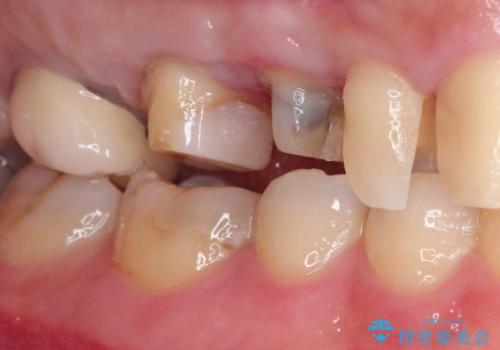

セラミッククラウン。虫歯の治療

- 定期検診にて不良補綴物、及び虫歯を認めオールセラミッククラウンにて治療を行いました。

右上第二小臼歯はカリエス除去中に露髄を認め、部分的断髄法にて歯髄を保存しております。